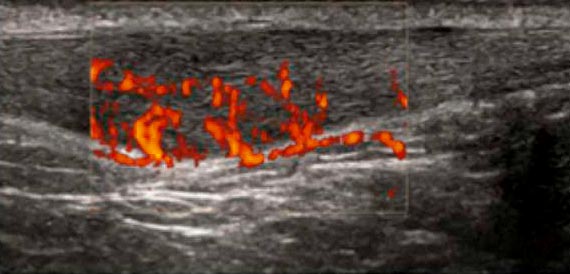

Sonographisch kann mittels power Doppler imaging(PDI)aus der Zahl der abgebildeten irregulären Gefäße auf die Anzahl der Nozizeptoren geschlossen werden. Hier beispielsweise typisch für degenerierte schmerzhafte Sehnenansatzerkrankungendie Epicondylitis lateralis (Tennisarm) und die entzündete Achillessehne (Achillodynie).

PDI Aufnahme: Irreguläre Gefäßbildung in der Achillessehe (Neovaskularisation) bei Achillodynie (Entzündung der Achillessehne).